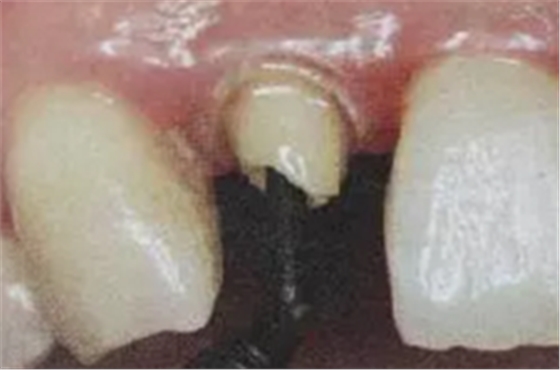

6. 纖維樁的試放和裁戴

纖維樁試放時(shí)應(yīng)用鑷子夾持將其插入預(yù)備的根管樁道中(這涉及無菌觀念和操作),就位時(shí)無阻力可稍有錮住感。

(鑷子夾持(正確))

(污染手套夾持(錯(cuò)誤))

(技工鉗裁剪(錯(cuò)誤))

試放后應(yīng)按所需長度用細(xì)粒金剛砂車針切割裁剪。

(粘樁堆核固化后裁剪)

為防止裁剪過程中有可能造成樁表面的污染,可以粘結(jié)固位后再進(jìn)行裁剪。

操作時(shí)。光固化燈應(yīng)在樹脂核成形后,頰、舌、合面分別光照20秒,在完成預(yù)備體后將其磨除。